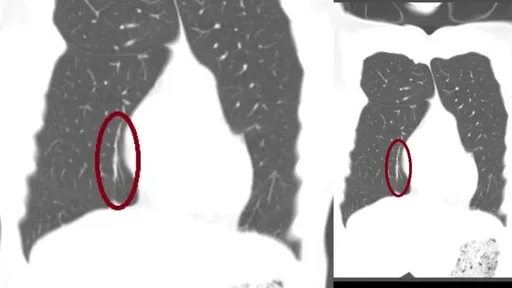

還原去年肺塌陷實況,張立昂自認身體健康,無家族病史,突然發生這狀況,不只他意外,醫生也意外。去年3月...

...奕兒考慮創一個兩家人的群組。 張立昂還是檢查不出肺塌陷主要原因,但天生基因的關係可能性較大。他說,...

張立昂去年三月因「肺塌陷」一度急插管治療,今年又因確診住院,如今身體狀況,他說:「還行,現在已經恢復...